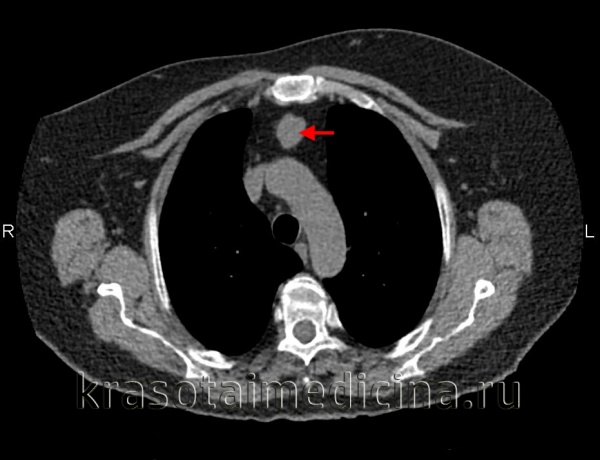

На компьютерных томограммах в аксиальной проекции визулизируются (Рис.7 — 13, 16-19):

1 – Правое легкое

2 – Левое легкое

4 — Левый главный бронх

5 – Правый главный бронх

6 – Непарная вена

7 — Нисходящая часть аорты

8 – Восходящая часть аорты

9 – Левый желудочек сердца

10 – Левое предсердие

11 – Правый желудочек

12 – Правое предсердие

13 – Легочный ствол, с отходящими от него левой и правой легочными артериями

15 – Плечеголовной ствол

16 – Левая общая сонная артерия

17 – Левая подключичная артерия

18 – Правая общая сонная артерия

19 – Правая подключичная артерия

20 – Верхняя полая вена

21 – Левая плечеголовная вена

22 — Правая плечеголовная вена